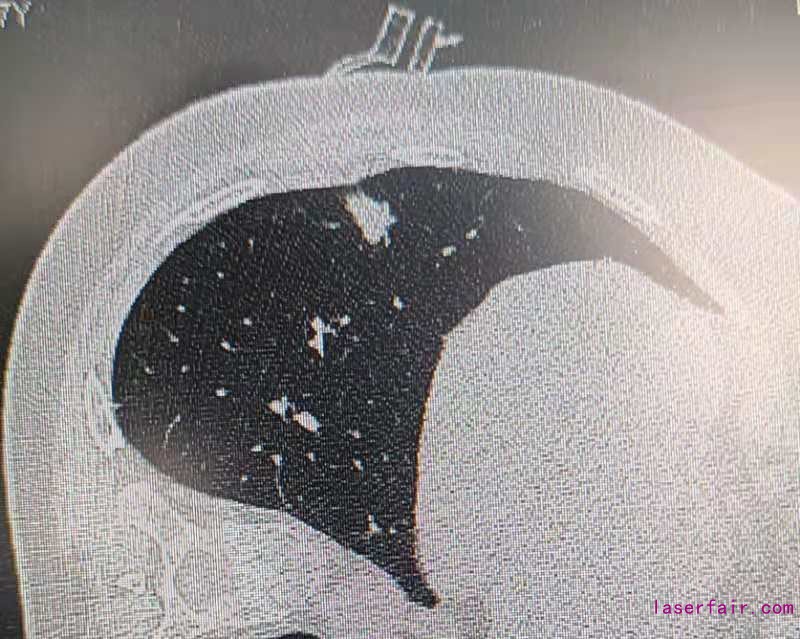

近日,蘭州大學第一醫(yī)院胸外科應用3D打印手術導航系統(tǒng),結合術中CT實現(xiàn)肺部病變的超精準定位。此項技術填補該省相關領域的空白。

伴隨胸部CT篩查的普及,早期肺部腫瘤發(fā)病率逐年增加,外科治療是唯一根治手段。這類疾病手術的難點在于病灶偏小(<1cm)、質地軟(磨玻璃型結節(jié)),外科術中難以精準確定病變位置及切除范圍。蘭州大學第一醫(yī)院胸外科利用3D打印技術,個體化定制肺小結節(jié)的術前定位導板,結合目前國際先進水平雜交手術平臺,術中CT設備輔助外科醫(yī)師術中定位肺結節(jié)位置。對比傳統(tǒng)定位技術,3D導板定位導航系統(tǒng)可極大簡化肺結節(jié)定位操作步驟,降低輻射暴露劑量,提高手術精度,減少肺部手術損傷。為患者加速康復打下了堅實的基礎。